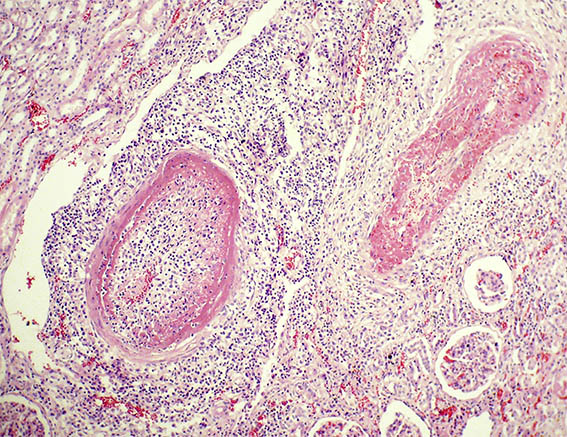

Figura 2. H&E, X200.